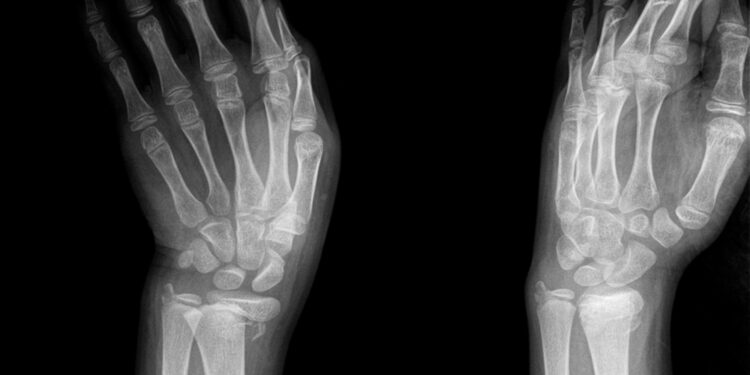

Kaip nustatoma Kienböcko liga?

Diagnozė prasideda nuo pokalbio apie simptomus su gydytoju. Tam tikrais atvejais, jei simptomai neaiškūs, gydytojas gali paskirti įvairius tyrimus:

- Riešo rentgenogramą;

- Magnetinio rezonanso tyrimą (MRT);

- Kompiuterinę tomografiją (KT);

- Kaulų skenavimą.

Tyrimų rezultatai padeda įvertinti ligos stadiją bei atmesti kitus susirgimus, tokius kaip kaulų lūžiai. Kienböcko liga įprastai skirstoma į 4 stadijas: nuo I (lengviausia) iki IV (sunkiausia). Paprastai stadijos nustatomos remiantis vaizdiniais tyrimais.